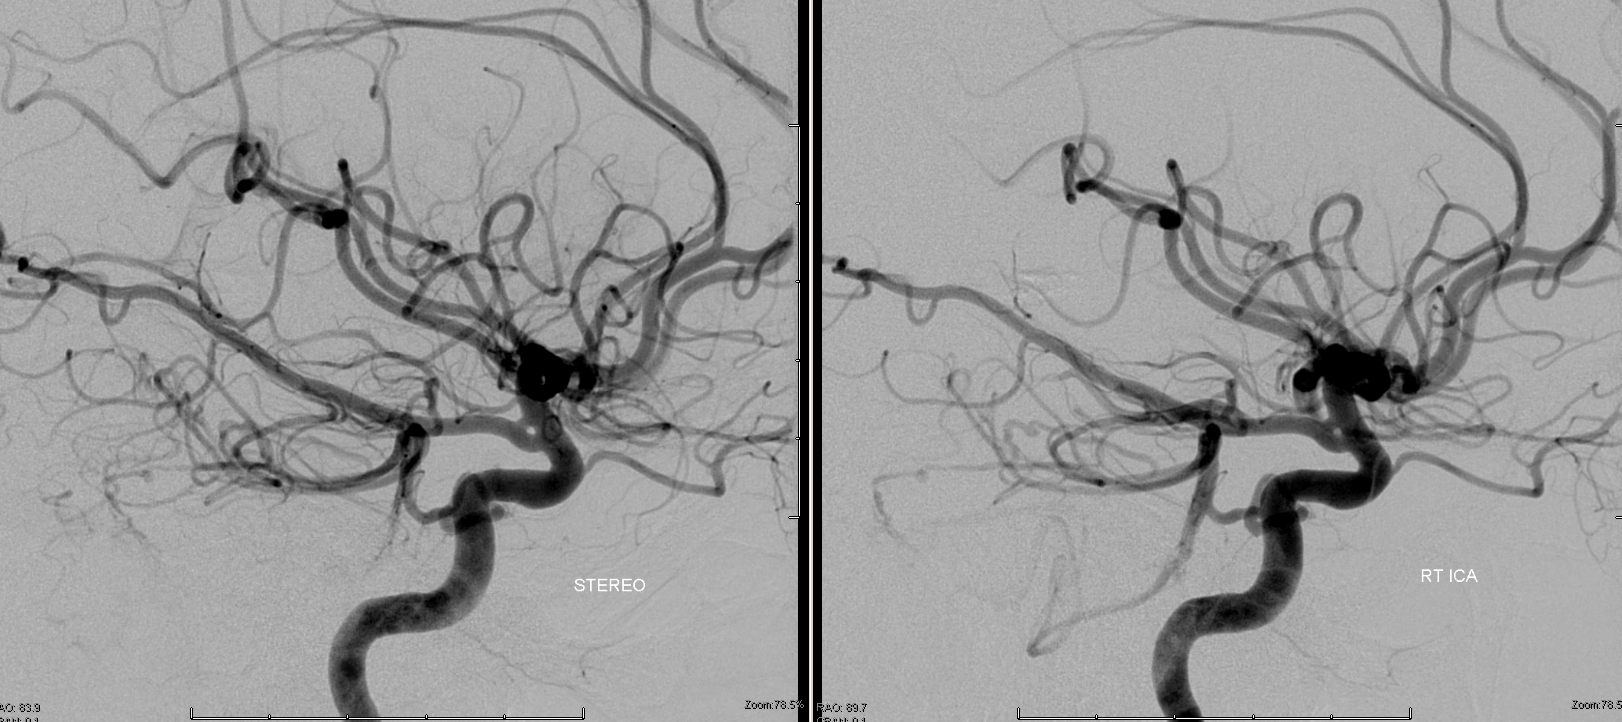

Below is a right PCA (P2) segment embolic occlusion. This is an artery to artery embolus from a diseased right cervical carotid (no arrows needed), via the trigeminal (dashed arrow), into the right P2 (arrow). The anatomy solves the riddle — left PCOM is fetal (no arrows needed), thus left P1 is hypoplastic and embolus of that size would not go there. it also could not have come from the verts because the basilar below trigeminal is hypoplastic as well (arrowhead) — in fact this was originally considered a basilar occlusion. However, clinical presentation was not consistent with that location and basilar hypoplasia below trigeminal is common. Excellent clinical correlation here.